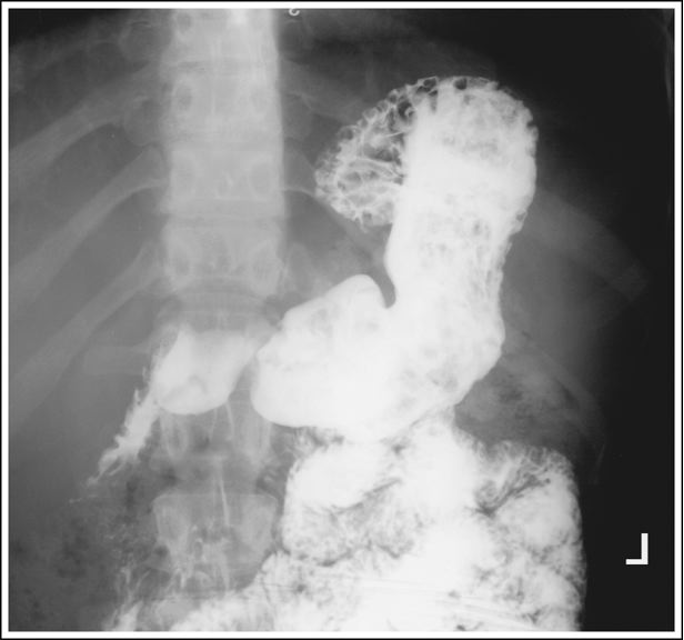

PA Oblique Stomach and Duodenum (CR and Positioning)

Recumbent RAO - Visualized the pyloric canal and duodenal bulb. No superimposition of pylorus and duodenal bulb. Gastric peristalsis is more active in this position.

Rotate 40-70 degrees - Hypersthenic patients requires more rotation

11×14 IR

CR - At the level 1-2 inches above lower rib margin (L1-L2) Midway between the vertebrae nd the lateral border of the elevated side

Mark Left Side

Suspend respiration at the end of expiration

Shield Gonads

Oblique stomach with proper positioning

Oblique stomach with bony cortices are sharp and the gastric and intestines are blurry. Peristaltic activity of the stomach and small intestines